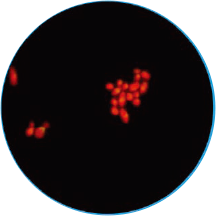

免疫荧光法结果展示及判读示例

阴道分泌物多重免疫荧光染色技术,具备形态学与荧光学的双重优势。可以同时对上皮细胞,白细胞,乳酸杆菌,线索细胞,念珠菌和毛滴虫等进行染色区分,既能检测阴道相关病原体感染,也能评估其阴道微生态和阴道清洁度等是否正常,为临床的快速诊断和治疗提供帮助。

毛滴虫

橙黄色荧光

梨形或椭圆形,直径

10~13 μm稍大于白细胞